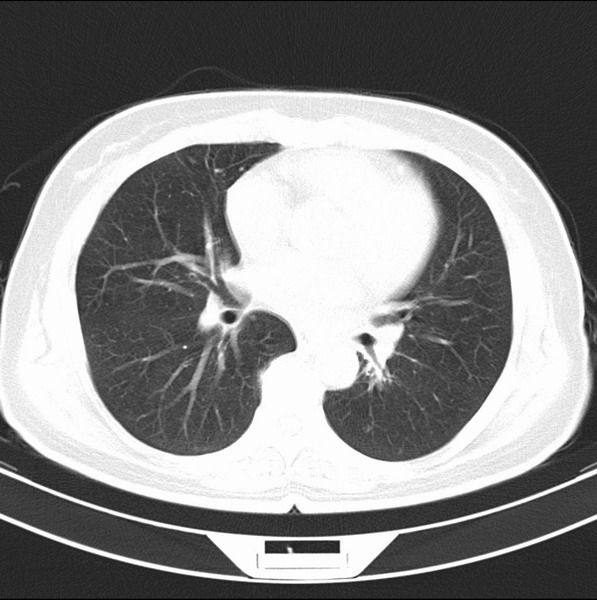

女、63

咳嗽、胸痛四个月

考虑左下肺中央型肺癌

支持左下中央型肺癌伴阻塞性炎症不张。

包绕左下肺基底段的不规则的软组织肿块,段支气管腔变形、狭窄及阻塞性炎症,病变区不规则强化,又是老年女性支持楼上看法。

典型病例:左下肺基底段中央型肺癌,相应支气管狭窄并阻塞性炎症